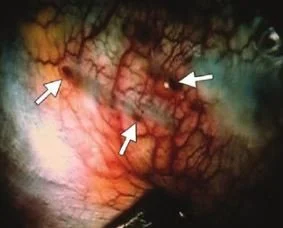

brownish endometrial implants on the lung in a 40 40 with spontaneous pneumothorax . Walker C. Tumorlike conditions of the pleura. Radiographics 2012 32:971-985